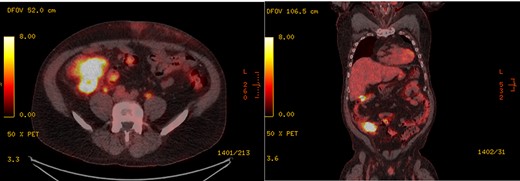

A 56-year-old male with a medical history of stage IV metastatic adenocarcinoma of the lung presented to the emergency department with acute appendicitis found on routine PET scan. The patient had a routine PET scan done that morning that showed new intense activity in the right lower quadrant (RLQ) inseparable from the cecum and appendix which was worrisome for acute appendicitis (Fig. 1). The patient reported minimal nausea and mild achy abdominal pain for the last 10 days; however, he had not sought treatment due to the mild nature of the pain. The patient denied any other symptoms including vomiting, fever, anorexia or bowel changes. The patient was taking Alectinib and Denosumab for cancer treatment and was known to have metastases to the axial and appendicular skeleton.

PET scan showing intense activity in the RLQ inseparable from the cecum and appendix, found to be acute appendicitis with XGI on histopathology of appendix specimen, in (left) axial section and (right) coronal section.